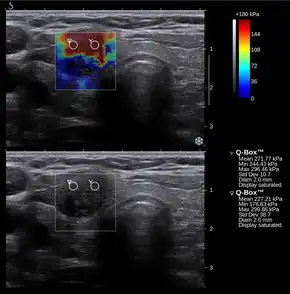

Conventional ultrasonography (lower image) and elastography (supersonic shear imaging; upper image) of papillary thyroid carcinoma, a malignant cancer. The cancer (red) is much stiffer than the healthy tissue.

Supersonic shear imaging (SSI)

Supersonic shear imaging of the stiffness during contraction of the hand muscles abductor digiti minimi (A) and first dorsal interosseous (B). The scale is in kPa of shear modulus.

Supersonic shear imaging (SSI)[8][9] gives a quantitative, real-time two-dimensional map of tissue stiffness. SSI is based on SWEI: it uses acoustic radiation force to induce a 'push' inside the tissue of interest generating shear waves and the tissue's stiffness is computed from how fast the resulting shear wave travels through the tissue. Local tissue velocity maps are obtained with a conventional speckle tracking technique and provide a full movie of the shear wave propagation through the tissue. There are two principal innovations implemented in SSI. First, by using many near-simultaneous pushes, SSI creates a source of shear waves which is moved through the medium at a supersonic speed. Second, the generated shear wave is visualized by using ultrafast imaging technique. Using inversion algorithms, the shear elasticity of medium is mapped quantitatively from the wave propagation movie. SSI is the first ultrasonic imaging technology able to reach more than 10,000 frames per second of deep-seated organs. SSI provides a set of quantitative and in vivo parameters describing the tissue mechanical properties: Young's modulus, viscosity, anisotropy.

This approach demonstrated clinical benefit in breast, thyroid, liver, prostate, and musculoskeletal imaging. SSI is used for breast examination with a number of high-resolution linear transducers.[10] A large multi-center breast imaging study has demonstrated both reproducibility[11] and significant improvement in the classification[12] of breast lesions when shear wave elastography images are added to the interpretation of standard B-mode and Color mode ultrasound images.